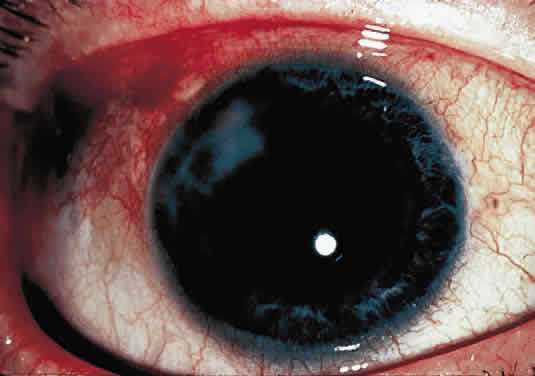

OCULAR FINDINGS. The outstanding clinical feature common to all three phenotypes is the corneal and conjunctival cystine crystal deposition (Figs. 3 and 4). Photophobia is often the only presenting visual symptom; this may be incapacitating and associated with blepharospasm.

Corneal deposits appear as a layer of homogeneously distributed, fusiform or needle-shaped, iridescent crystals situated in the stroma beneath the epithelium. In the infantile form, anterior crystal deposition begins early in life (between 6 and 15 months of age) and proceeds posteriorly as the patient ages; deposition advances more rapidly in the periphery. The anterior location of the crystals may be associated with recurrent erosions.33 The depth of the stromal deposition and the density of crystals is always greater peripherally than centrally. More and larger crystals occur in the superficial stroma. No visual impairment occurs at this early stage. By the age of 7 years, most patients have crystals, either within or on the endothelial surface34,35; markedly decreased corneal sensitivity is also present.36 The spherical contrast sensitivity function is significantly lower in infantile cystinosis than in age-matched controls.37